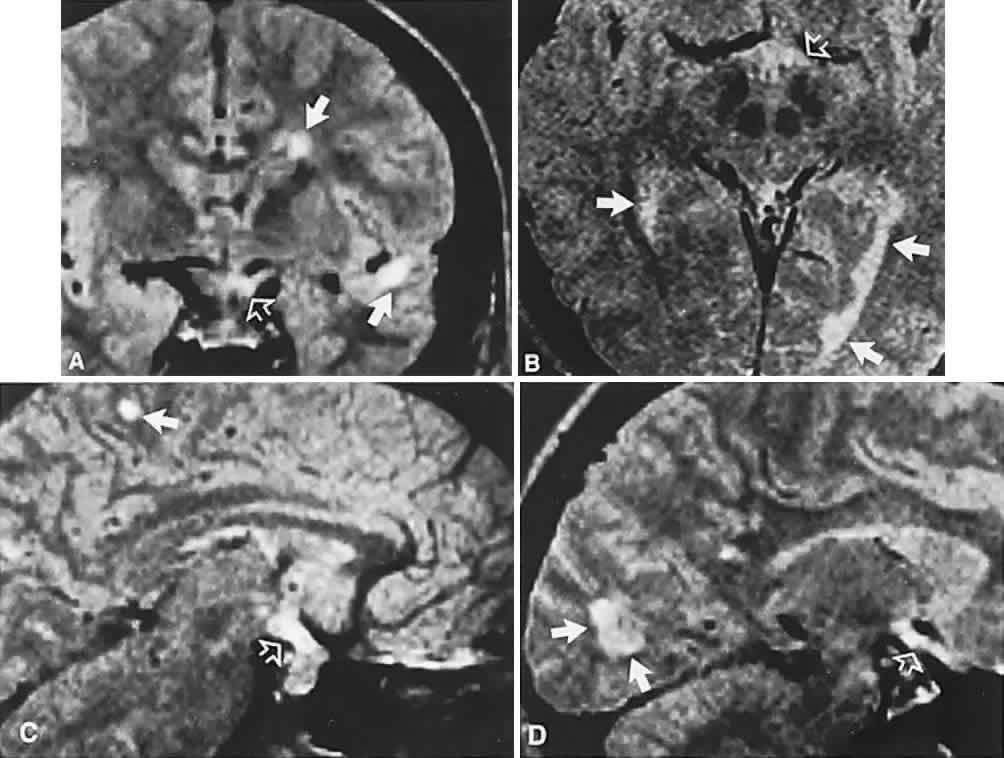

The absence of field defects, for example, in patients undergoing evaluation for amenorrhea, galactorrhea, or sellar enlargement incidentally discovered, does not imply the absence of an adenoma. Obviously, patients with microadenomas, that is, confined within the sella, do not have field defects. From a study24 of 50 cases of pituitary adenomas with chiasmal syndrome, it was concluded that visual disturbance occurs when the chiasm is displaced approximately 10 mm upward (see also Volume 2, Chapter 4, Fig. 6). The modern management of pituitary adenomas should involve several disciplines: current neuroradiologic studies detect microadenomas and provide precise delineation of gross morphology and status of neighboring structures, and mixed MRI signals suggest new or old hemorrhage, cysts, and so forth (Fig. 2); radioimmunoassay techniques assay PRL and other endocrine levels; oral neuropharmacologic agents, such as bromergocryptine, provide a “medical adenomectomy” for hyperprolactinemia and acromegaly; transsphenoidal surgery, including high-illumination microscopical procedures, televised radiofluoroscopic monitoring, and infection control, has all but replaced transcranial approaches; immunohistochemistry techniques have replaced the anachronistic tinctorial designations (e.g., chromophobe, basophilic) with a functional classification.

Fig. 2. Large prolactinoma. Original vision in the right eye (RE) was 8/200, left eye (LE) 1/200, with serum prolactin of 26,000 ng/ml and galactorrhea. Four months of bromocriptine reduced prolactin to 661 ng/ml, vision improved to RE 20/40, LE 20/50. At 3 years, vision was as follows: RE 20/30, LE 20/20; prolactin was 25.9 ng/ml. Enhanced magnetic resonance imaging. Sagittal (A) and coronal (C) images at diagnosis. Sagittal (B) and coronal (D) images at 2-year follow-up, showing dramatic shrinkage of the mass.